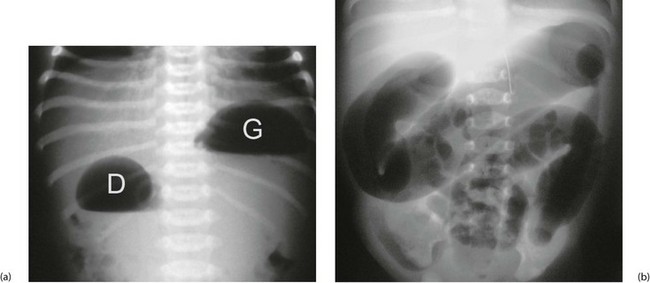

The important causes of upper intestinal obstruction in babies are duodenal atresia and malrotation with volvulus. Causes of low obstruction include Hirschsprung's disease and meconium ileus. Small bowel atresia may affect jejunum or ileum, causing high or low obstruction respectively. Plain abdominal X-rays usually confirm intestinal obstruction. When obstruction is high, there is a lack of distal intestinal gas (Fig. 50.1a); when low, there are dilated loops of bowel (Fig. 50.1b). If malrotation is suspected, an upper GI contrast study can determine the abnormal position of the duodeno-jejunal flexure. Other causes such as incarcerated inguinal hernia or imperforate anus can be detected by clinical examination. A plan for managing babies with suspected obstruction is outlined in Fig 50.2.

Fig. 50.1 Intestinal obstruction

(a) Erect plain abdominal X-ray of a baby with ‘high’ intestinal obstruction, showing the typical ‘double bubble’ appearance of gas in the dilated stomach G and the first part of the duodenum D. The differential diagnosis includes duodenal atresia, malrotation with volvulus obstructing the duodenum and a very high jejunal atresia. Fluid levels are seen in this erect film.

(b) Abdominal X-ray of a baby with a ‘low’ intestinal obstruction, showing several dilated loops of bowel. The differential diagnosis includes Hirschsprung's disease, meconium ileus and ileal atresia

Duodenal obstruction: Duodenal atresia causes obstruction of the second part of the duodenum, usually just below the common bile duct entry resulting in bile-stained vomiting. The anomaly is a web across the lumen or complete separation of the bowel ends. If the web is incomplete, there is initial poor feeding and failure to thrive until a milk curd impacts, causing obstruction. Plain abdominal X-ray shows a double bubble, with one air–fluid interface in the stomach and another in the duodenum (Fig. 50.1a).

Obstruction may be present from birth or delayed a few days if a web is incomplete. Presenting signs depend on the level of obstruction: high jejunal obstruction presents like duodenal atresia or malrotation with bile-stained vomiting and a lack of gas on X-ray (Fig. 50.1a); low ileal obstruction presents like meconium ileus or Hirschsprung's disease, with failure to pass meconium, poor feeding, abdominal distension and dilated intestine on X-ray. Small bowel atresia is sometimes associated with cystic fibrosis, and patients should have a genetic screen and a sweat test to exclude it.

Acute volvulus: Children with malrotation may undergo acute volvulus at any time, in which the mass of bowel twists on its axis, occluding the superior mesenteric (midgut) vessels, causing intestinal ischaemia and infarction. This is a surgical emergency presenting as high intestinal obstruction with bile-stained vomiting. Plain radiographs show features similar to any other high obstruction (Fig. 50.1a). Previously well children who present acutely with sudden duodenal obstruction, particularly with signs of peritonitis, should have very urgent surgery to prevent midgut infarction. At operation, the bowel is untwisted and any gangrenous bowel resected. Surgery also involves dividing Ladd's bands. This broadens the mesenteric base by moving the duodenum to the right and caecum to the left. A stable situation is thus created, reducing the risk of recurrent volvulus. If there is insufficient small bowel remaining, short bowel syndrome (intestinal insufficiency) is likely.